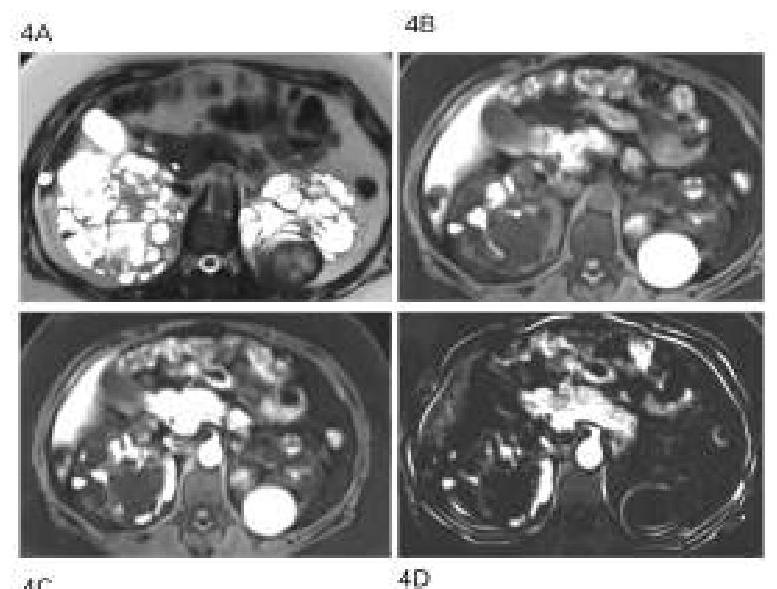

A 45-year-old patient presents with hypertension, hematuria, and flank pain. An MRI scan is performed, and the image provided shows multiple cystic lesions in both kidneys. What is the most likely diagnosis?

Explanation: ***Autosomal Dominant Polycystic Kidney Disease (ADPKD)*** - The presence of **hypertension, hematuria, and flank pain** in conjunction with an MRI showing **multiple bilateral renal cystic lesions** is highly characteristic of ADPKD. - ADPKD is a genetic disorder leading to the gradual enlargement of **cysts in both kidneys**, often accompanied by complications such as pain, bleeding into cysts, and eventually **renal failure**. *Renal cyst* - A **simple renal cyst** is typically a solitary, benign lesion and would not explain the **hypertension, hematuria, or multiple bilateral cysts** seen on imaging. - While common, a simple cyst usually causes no symptoms unless it becomes very large or ruptures. *Renal tumor* - A renal tumor, such as **renal cell carcinoma**, typically presents as a **solid mass** or a complex cystic mass, not multiple simple cysts bilaterally. - While it can cause hematuria, flank pain, and hypertension, the imaging description of **multiple cystic lesions in both kidneys** points away from a single tumor. *Chronic kidney disease with cystic degeneration* - While **chronic kidney disease (CKD)** can sometimes be associated with acquired renal cysts, especially in patients on dialysis, these cysts are typically **smaller, fewer in number**, and develop over a longer course than what is implied here. - This condition does not typically present with the extensive, bilateral cystic burden seen in ADPKD as the primary pathology. *Acquired cystic kidney disease* - **Acquired cystic kidney disease (ACKD)** typically develops in patients with **end-stage renal disease**, particularly those on **long-term dialysis**. - While it can present with bilateral renal cysts, it usually occurs in the context of **pre-existing chronic kidney disease**, and the patient would have a known history of renal dysfunction. - The clinical presentation here, with a 45-year-old presenting acutely with hypertension, hematuria, and flank pain without mention of dialysis or CKD history, favors **ADPKD** over ACKD.

Explanation: ***Autosomal dominant polycystic kidney disease*** - The patient's presentation with **pain**, **hematuria**, and **hypertension** is typical for **ADPKD**. The family history of a brother dying of a **stroke** at a young age suggests a genetic predisposition to vascular abnormalities, common in ADPKD. - **Cerebral aneurysms**, which can lead to stroke, are a known extranal manifestation of ADPKD, and early onset stroke in a sibling strengthens the diagnosis despite it not being the defining feature of ADPKD itself. *Renal cell carcinoma* - While **hematuria**, **loin pain**, and **hypertension** can be symptoms of renal cell carcinoma, the bilateral nature of the cysts seen in the image and the family history of **early stroke** make ADPKD a more probable diagnosis. - Renal cell carcinoma usually presents as a **unilateral** solid mass, not diffuse cystic changes in both kidneys. *Tuberculosis of the kidney* - Renal tuberculosis would present with symptoms like sterile pyuria, dysuria, and flank pain, but less commonly with the dramatic cystic changes and family history of stroke seen here. - The imaging would typically show cavitary lesions or hydronephrosis rather than widespread bilateral cysts. *Autosomal recessive polycystic kidney disease* - **ARPKD** typically presents in **infancy or childhood** with severe renal failure and liver involvement. - The patient's age (40 years) makes ARPKD highly unlikely, as individuals with this condition rarely survive into adulthood without significant medical intervention.